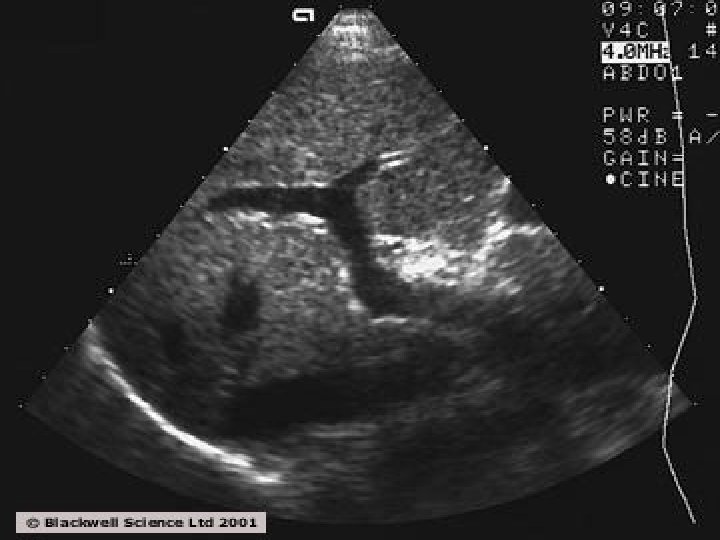

Abdominal ultrasound : �Mixed echopattern. �Dilated portal vein. �Enlarged spleen. �Ascites.